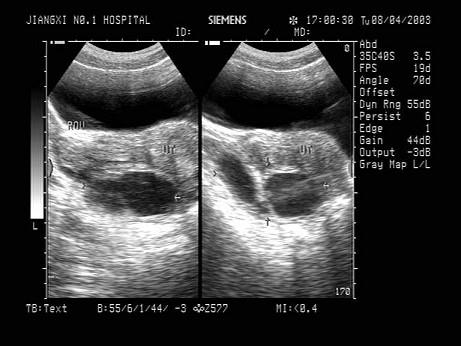

女性,40岁,反复下腹部疼痛、白带异常3年余。超声检查如图,最可能的诊断为?(?)A.输卵管积液B.囊腺瘤C.畸胎瘤D.子宫肌瘤E.附件囊肿

问题 女性,40岁,反复下腹部疼痛、白带异常3年余。超声检查如图,最可能的诊断为?(?)

选项 A.输卵管积液 B.囊腺瘤 C.畸胎瘤 D.子宫肌瘤 E.附件囊肿

答案 A